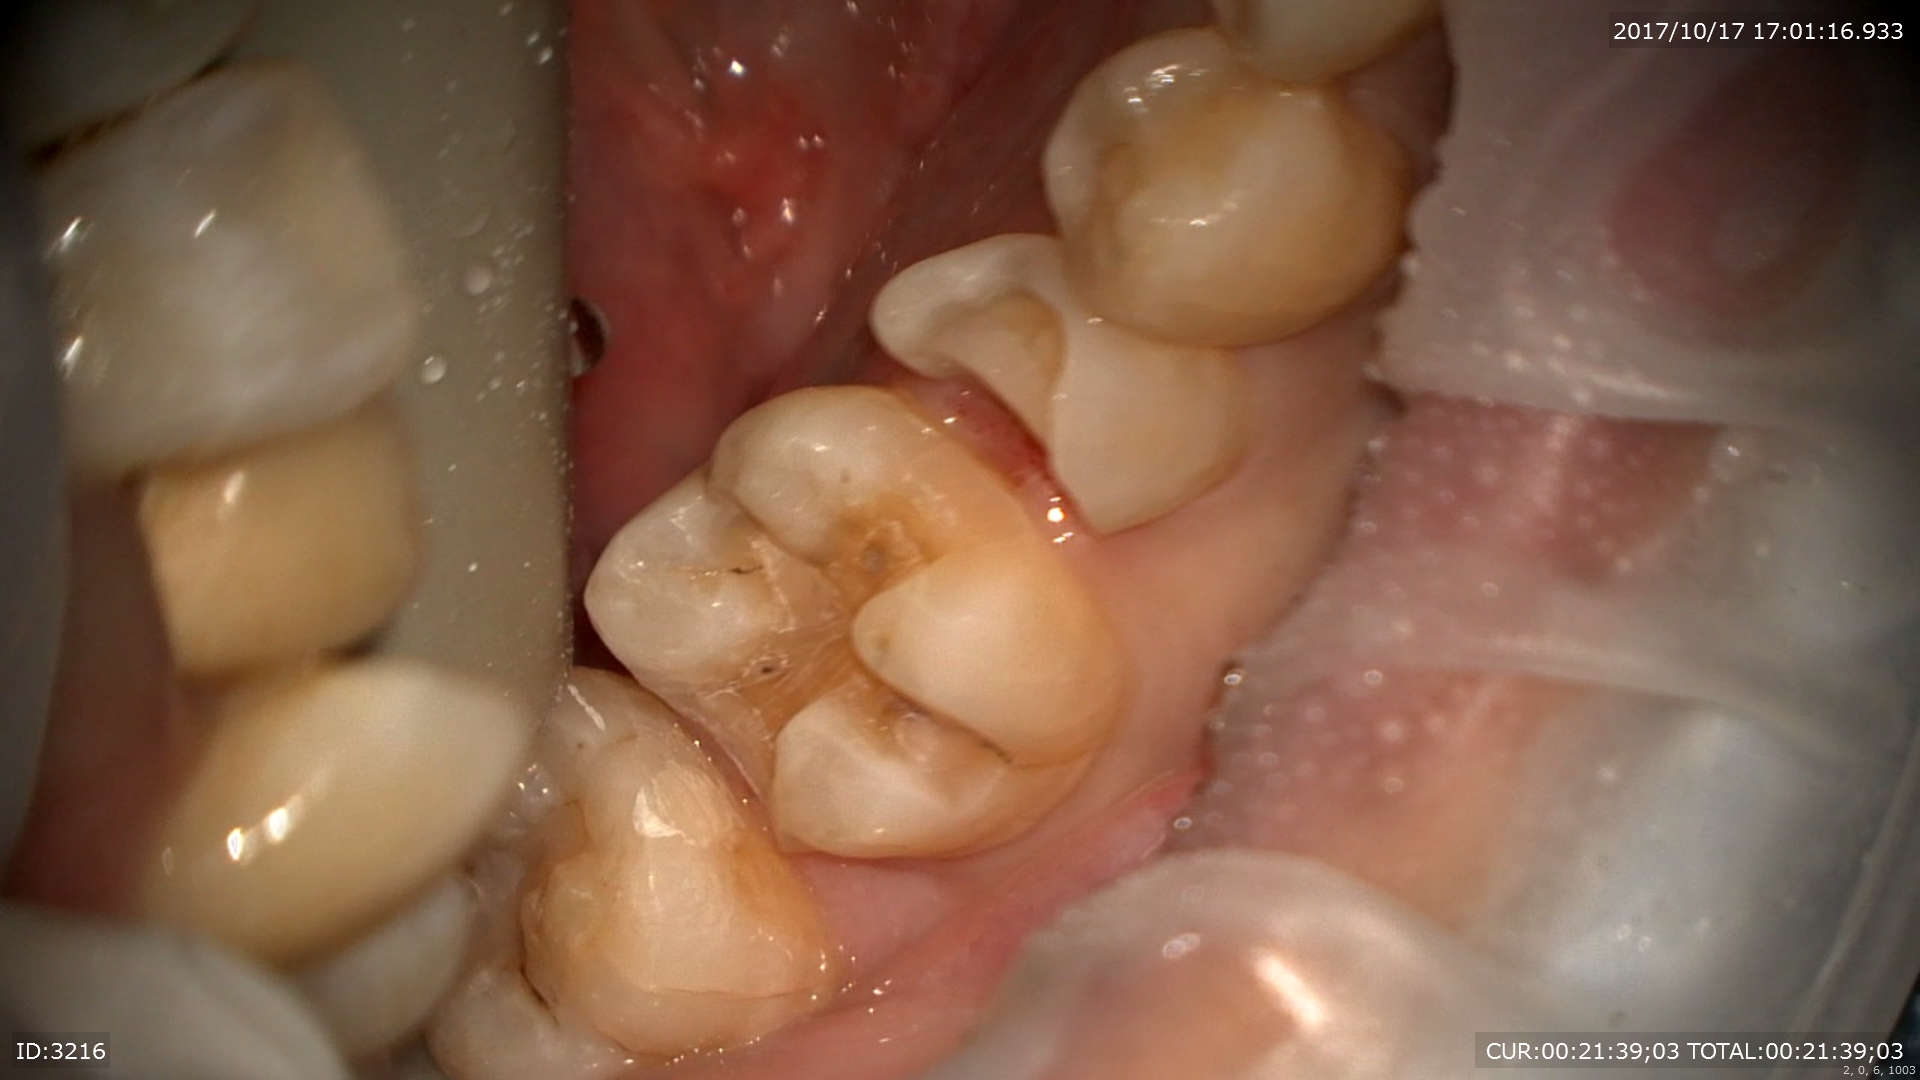

本日修復終了

術前(右)術後(左)

このように当院ではむし歯治療においても術後までを考え治療を行っております。